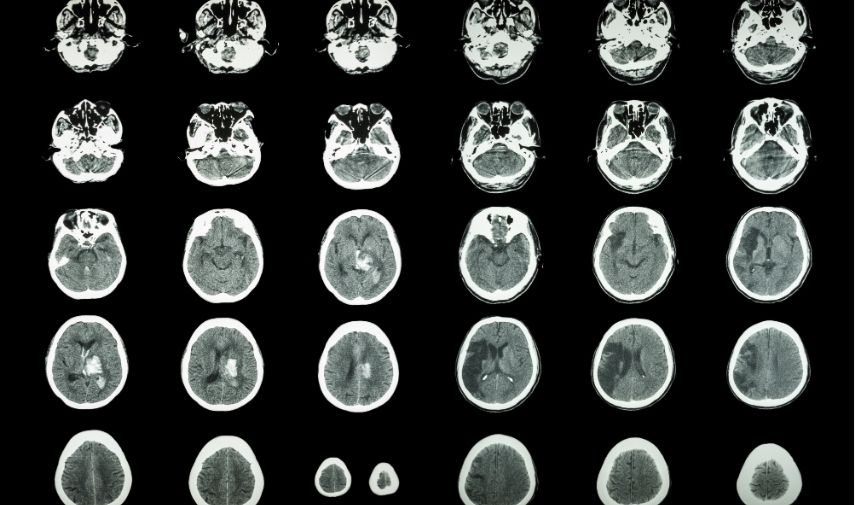

AIT: señal temprana de un derrame cerebral. Un AIT ocurre cuando se interrumpe temporalmente el flujo sanguíneo hacia una parte del cerebro. Esta interrupción provoca síntomas similares a los de un accidente cerebrovascular (ACV), tales como:

¿Qué hacer ante un ataque isquémico transitorio? A diferencia de un ACV, estos síntomas desaparecen por completo en menos de 24 horas y no dejan secuelas permanentes. Pero eso no significa que debas ignorarlo: un AIT es una fuerte advertencia de que podrías sufrir un ACV en el futuro cercano.